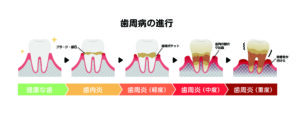

歯周病は無自覚のうちに進行しやすい病気です

歯科疾患の全国的な実態調査では、4mm以上の「歯周ポケット」がある人は全体の47.9%と報告されています。

歯周ポケット(PPD)は、歯と歯ぐきの境目の溝の深さを測る指標です。

一般に、4mm以上の歯周ポケットは歯周病が疑われる目安とされ、歯周組織に炎症が起きている可能性がある状態です。

ただし、歯周ポケットの深さだけで、歯周病の進み具合を決めることはできません。

歯医者では、出血の有無や歯ぐきの下がり方、レントゲンで骨の状態もあわせて確認し、総合的に判断します。

この数字が意味するのは、「約2人に1人が、歯周病に関連するお口の変化をすでに抱えている可能性がある」ということです。

歯周病が進行すると、「歯と歯ぐきの間」に溝(歯周ポケット)が形成され、深くなっていきます。

歯周ポケットは歯ブラシが届きにくく、細菌が増えやすい環境です。

歯周病は、初期の段階では強い痛みが出にくい病気です。

そのため、「痛くないから大丈夫」と思っている間に、歯周ポケットが深くなり、細菌が増えやすい状態が続いていることもあります。